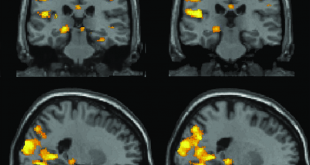

دکتر میر شهرام صفری | Dr. Mir Shahram Safari 2017/10/16 دیدگاه 5,350 بازدید

Tags brain hack DARPA downloadable learning enhanced leanrning learning meta human Neuroplasticity stimulation synaptic plasticity Targeted Neuroplasticity Training TNT training آپلود روی مغز ابر انسان انعطاف پذیری سیناپسی تحریک مغزی دارپا سرباز یادگیری سریع یادگیری قابل دانلود